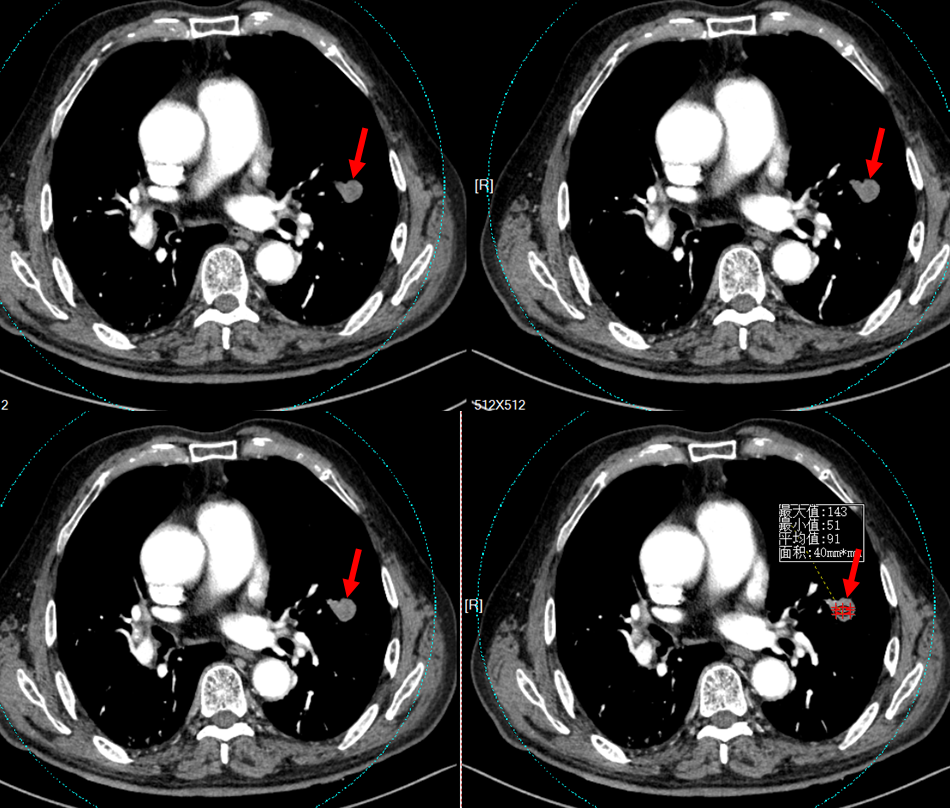

• 影像学检查:3536585,2025-11-10 胸部CT增强

影像学表现

图片来源:东南大学附属中大医院放射科